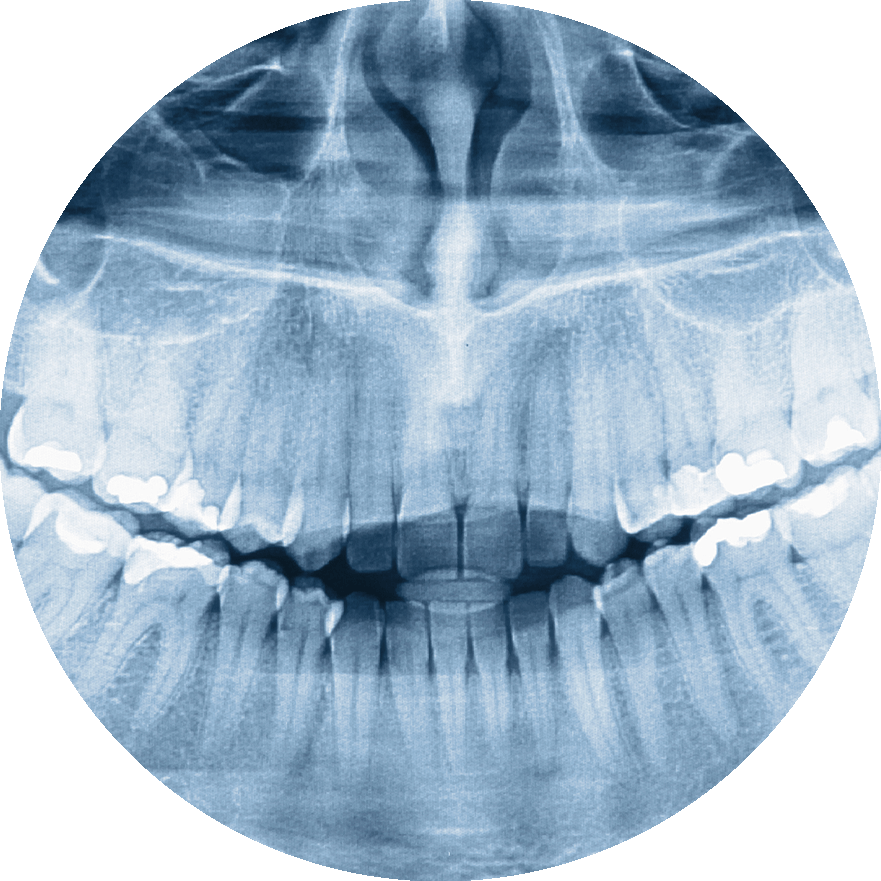

CBCT 3D imaging is the most advanced device in dentistry that shows accurate 3D images of your jawbone and teeth in less than 20 seconds with less radiation than traditional 2D X-rays.

At Blooming Dental & Implant Center, we use KAVO OP3D CBCT 3D Imaging to properly plan and minimize complications during your Dental Implants, Root Canals, and Wisdom Teeth Extractions procedures. CBCT 3D Imaging also helps us quickly find sources of even the most complicated toothaches to get you out of pain faster.

Digital X-rays

Digital X-rays make clear images of your jawbone and teeth to find cavities, gum disease, and other problems with 90% less radiation than traditional film X-rays. Blooming Dental & Implant Center is proud to offer the class-leading DEXIS Titanium Digital X-ray sensor. DEXIS Titanium is the most advanced sensor that produces phenomenal image clarity and has rounded corners for comfort for adults and children.